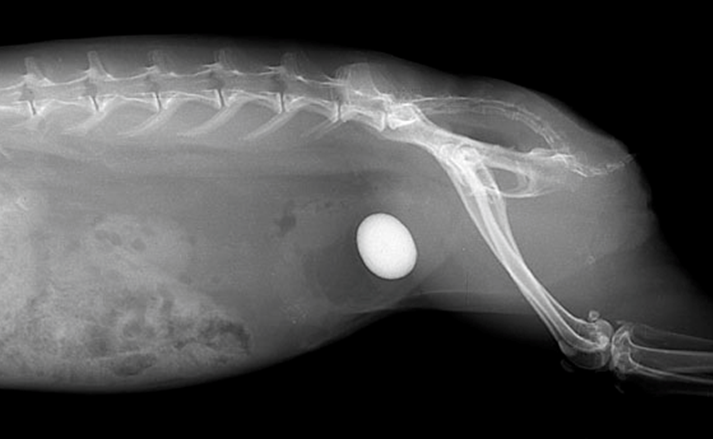

尿路結石症とスラッジ形成の病態生理学

ウサギの維持期のカルシウム要求量は0.4~0.8%とされています 。この要求量を超えるCaを慢性的に摂取すると、尿中へのCa排泄量が過剰となり、高Ca尿症を引き起こしませ 。ウサギの尿中Caは、主に炭酸カルシウムの形で存在します。尿中Ca濃度が高すぎると、この炭酸カルシウムが沈殿しやすくなり、その結果、尿路結石、膀胱スラッジといった主要な臨床問題が頻繁に観察されます。

尿石症予防においては、絶対的なカルシウム摂取量を厳しく制御し、0.8%以下に維持することが臨床的に最も重要です。高Ca食の原因特定は、ペレットだけでなく、アルファルファの牧草や高Ca野菜の過剰供給にも起因していることが多いため、維持期ウサギからこれらの高Ca源を意図的に排除することが必須となります。